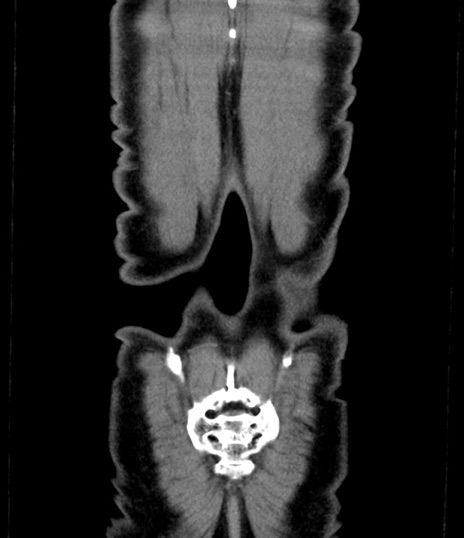

横断像